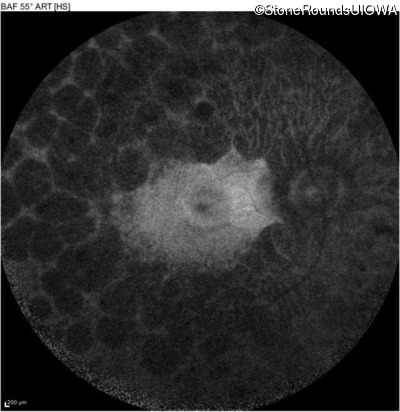

Infrared Fundus Photograph - Right - 20/63

Exemplar

Infrared Fundus Photograph - Left - 20/50 -2